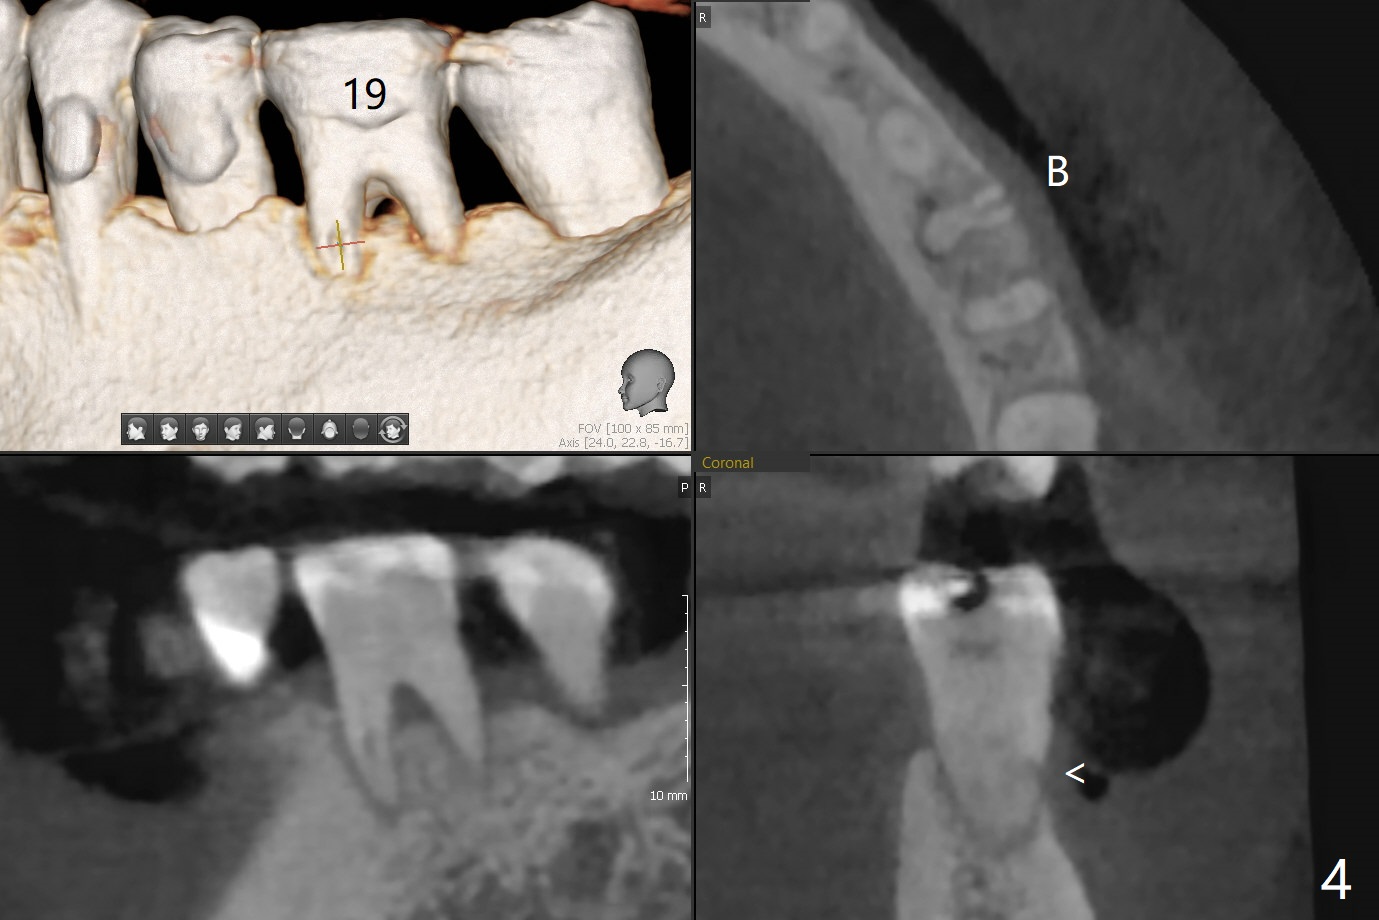

57岁女全口牙龈萎缩骨质吸收,其实卫生好,3号牙金属圈多年,治疗牙齿隐裂,骨质吸收和牙裂与咀嚼力大有关。最近抱怨19,30号牙敏感(图一),涂脱敏剂无效,拍摄根尖片(图二,三),显示30号牙远中根,19号牙近中根从牙槽嵴开始仿佛纵裂(图二,三),牙周探针患根周围触痛。磨牙牙根好像一段式植体,断裂总是发生于牙槽嵴顶,不过是横裂,所以一定要植入牙槽嵴之下,还要考虑今后牙槽嵴吸收。如何确诊牙根纵裂呢?例如19号牙CT显示颊侧近中根(图四,六:B)牙槽嵴处断裂(箭头)。利用一个叫Profile Program(Profilogram)测定近中根横断面平均密度,舌侧密度基本均匀(图七),而颊侧断裂处密度突然降低(图八)。当断裂还不是很明显时(隐裂),测定平均密度就显得重要,帮助诊断。